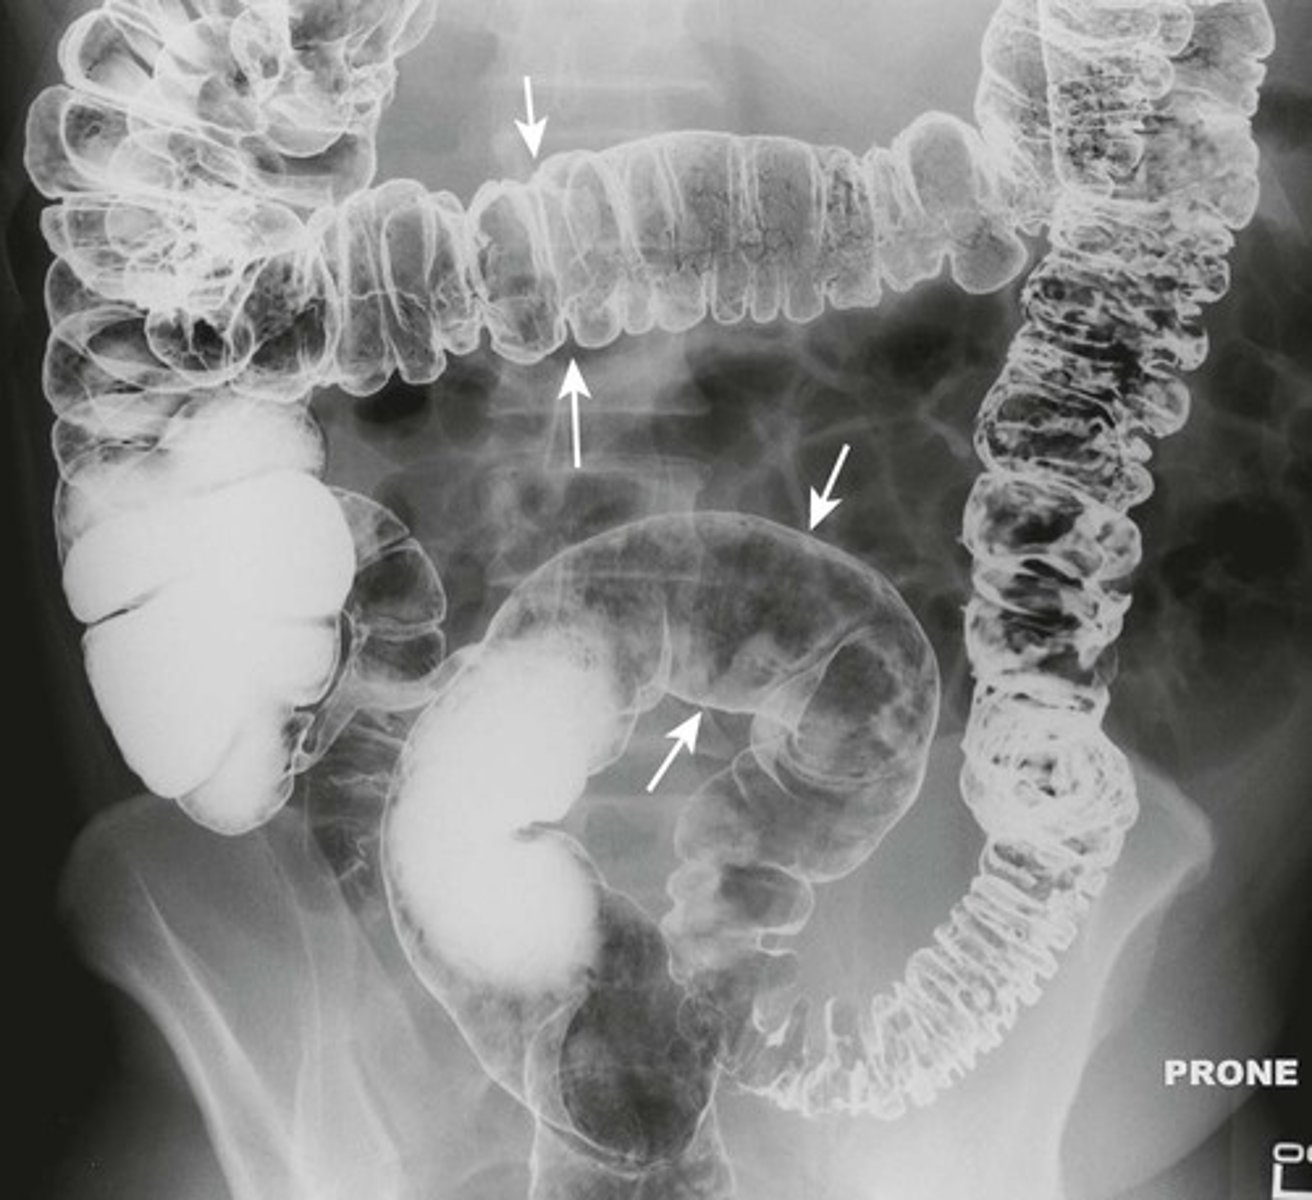

Normal colonic distension from barium study.

WHITE ARROW: normal distension of colon